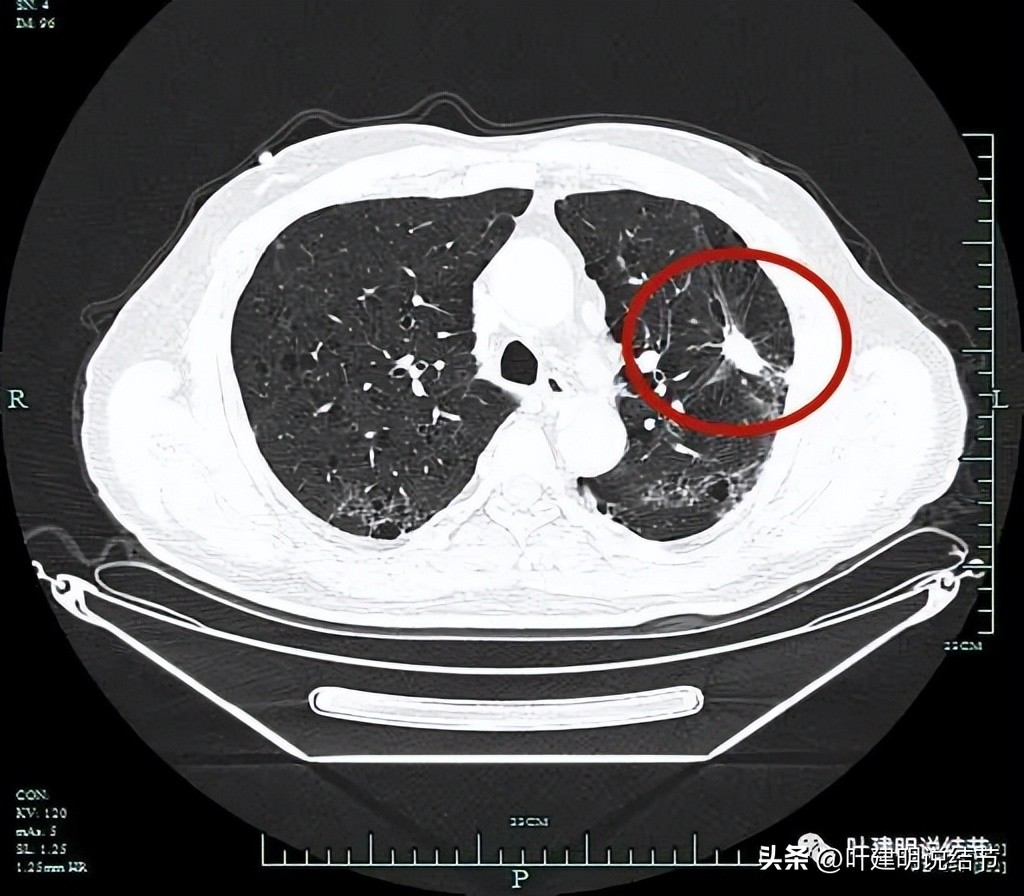

左上病灶开始出现,周围伴慢性炎的表现(红色圈起来部位);其他余部分有多处炎性改变(粉色圈起来的)。

病灶实性,边上有炎性改变。

余肺多处间质性炎症或新冠后没有吸收的表现。

上图是非左上病灶层面的多发炎性影像表现(后来考虑是不是与肺门纵嫩淋巴结肿大并葡萄糖代谢相关)。